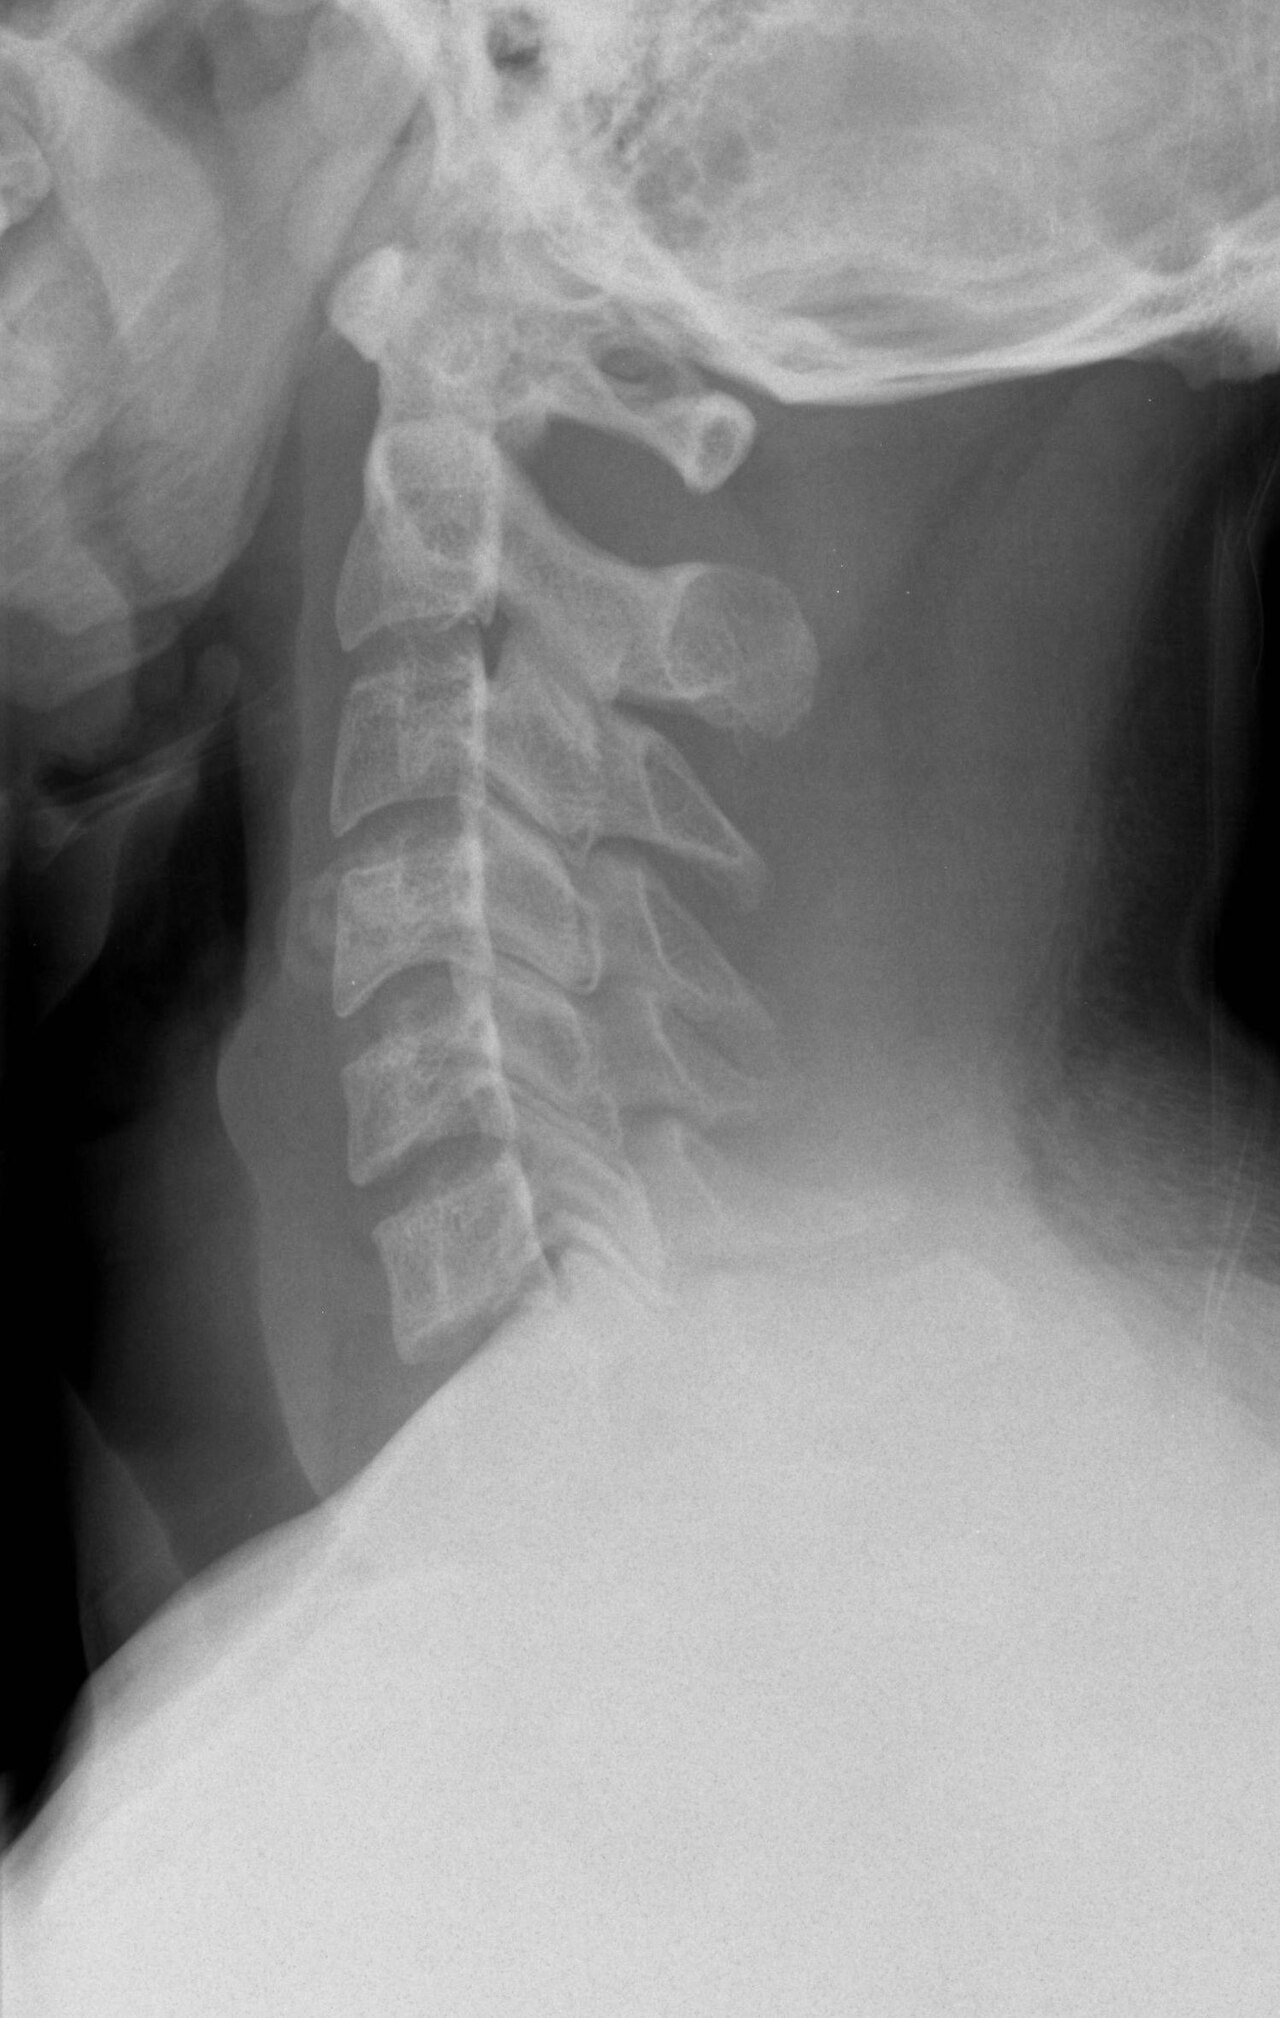

Cervical spine phantom with vertebral bodies C1-C7, intervertebral discs, spinal cord, nerve roots, and vertebral arteries